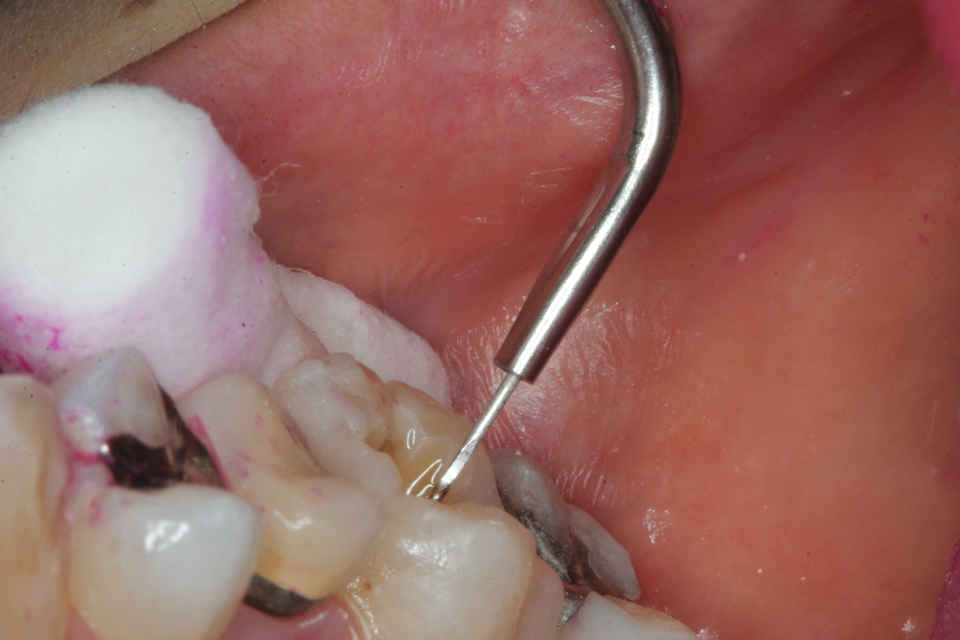

残根上のCR(ダイレクトボンディング)8 2025.11.12

ブリッジ脱離で2次カリエス+Perでグラグ… 2025.11.01

ブリッジ脱離で2次カリエス+Perでグラグ… 2025.10.31